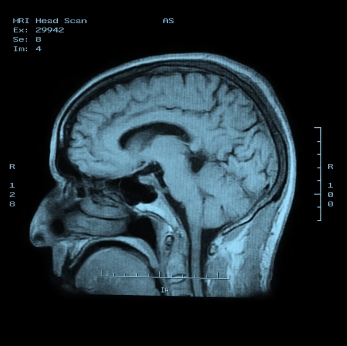

МРТ головного мозга с красителем

Описание услуги - МРТ головного мозга с красителем

МРТ является магнитно-резонансная томография, специальный тест визуализации, которая не использует рентгеновских лучей. Эта процедура дает очень подробные изображения мозга, структуры лица, и пазух. В целом, МРТ лучше, чем КТ при определении острых приступов, инфекции и рак. Внутривенно краситель называется гадолиний иногда используется для получения лучшего изображения.